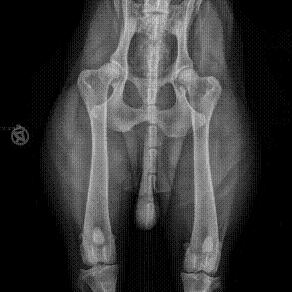

| Parasiten | Skeletterkrankungen |